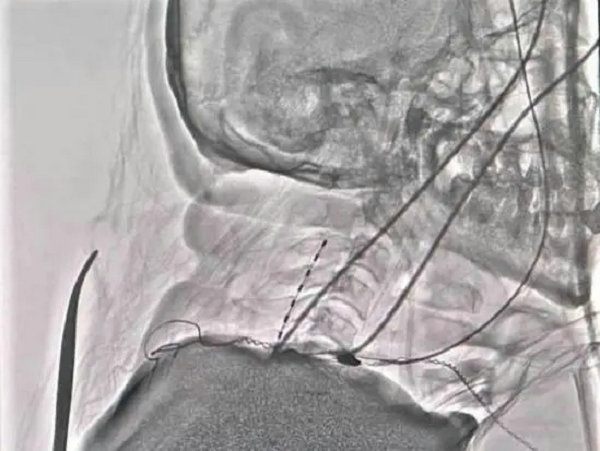

4月27日在医院复合手术室,由寿记新主任医师、管海博主治医师共同完成颈段及腰段短时程脊髓电极植入术,为患者尽早拔除气管套管、完全清醒、站起来、能走路、回归生活奠定了良好基础。

病例二:老年男性,1个月前“因高处坠落致颅脑及胸段脊髓损伤后双下肢截瘫”,由外院转入神经外科一病区,后经积极评估、讨论后给予胸段椎管扩大减压+内固定术。术后虽左下肢可稍活动,但右侧下肢仍无明显活动、大小便排便困难,需持续卧床,家属进行照顾。患者及家属治疗愿望迫切,1周前科室再次充分讨论下一步治疗方案,最后决定行腰段短时程脊髓电刺激手术治疗。